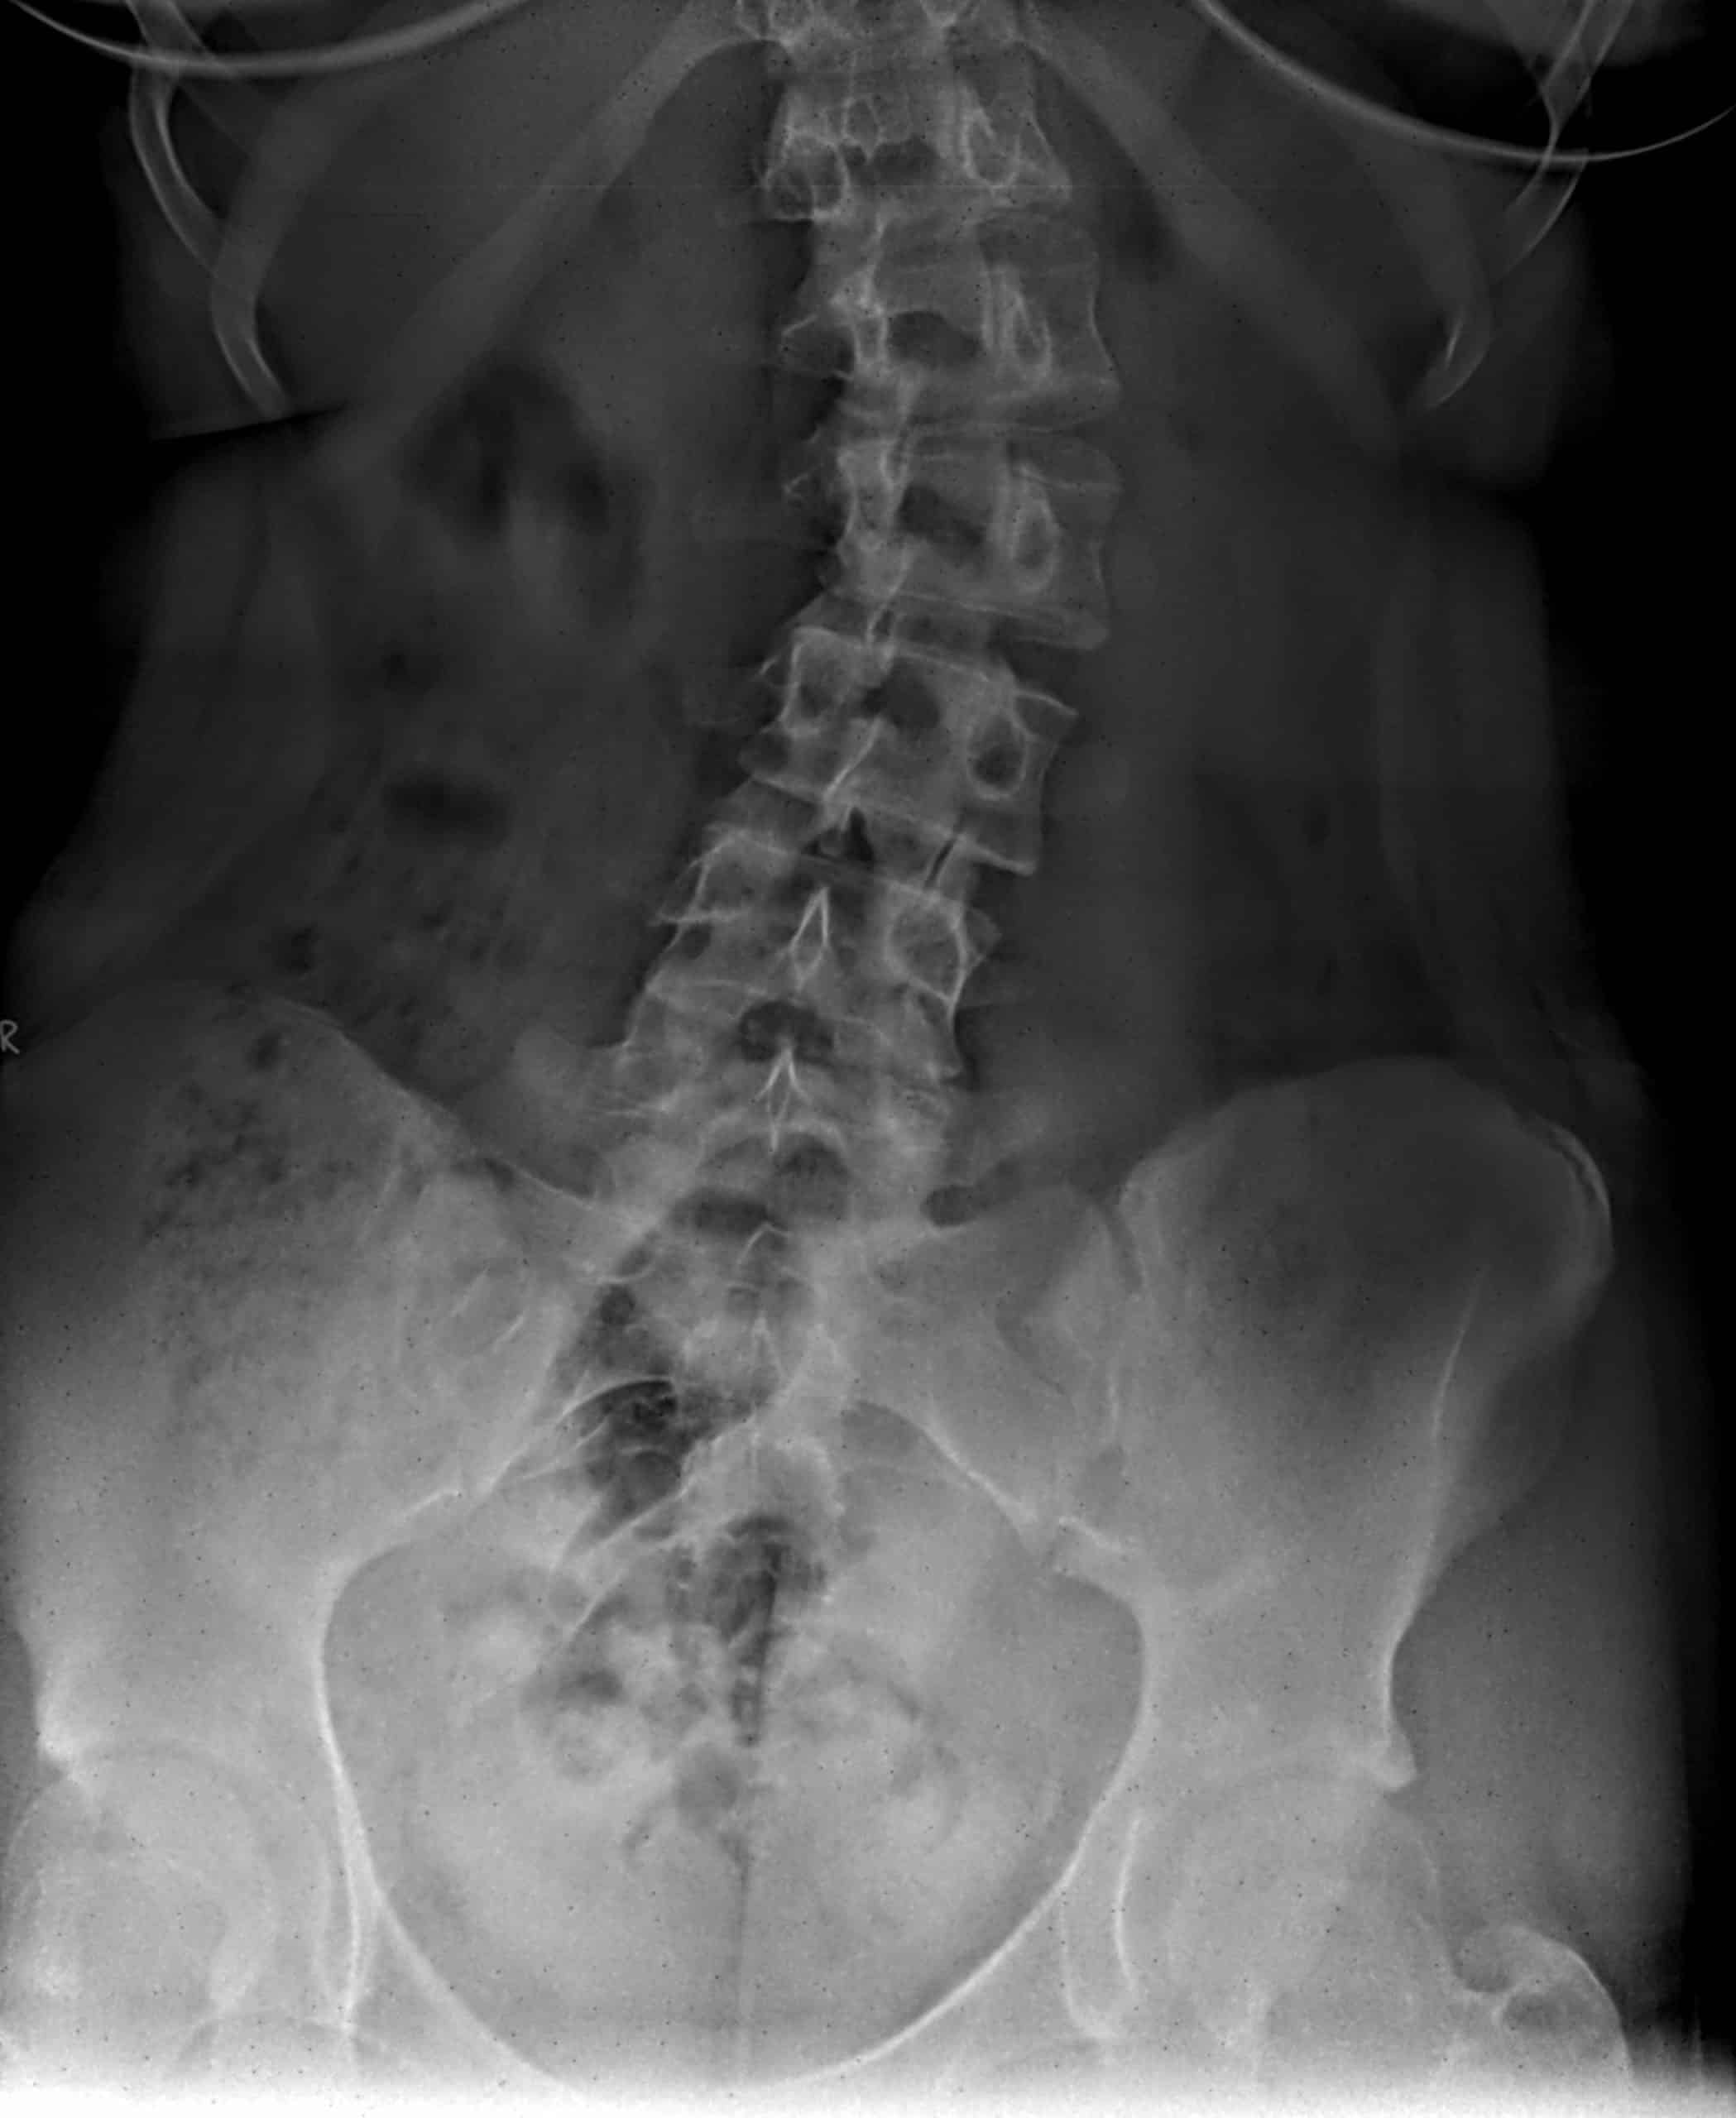

Read More →How Can Chiropractors Help Scoliosis?

Everyone’s spine curves a little bit, but sometimes said curve goes beyond the normal amount. The curvature of your spine is what keeps your head positioned over your pelvis and is what helps to absorb any shock from the stress the biomechanics of moving place on your spine. If your spine is curved too much, so that it starts to look more like a C or an S, then this can result in a number of problems, since it impacts how your spine is meant to function.